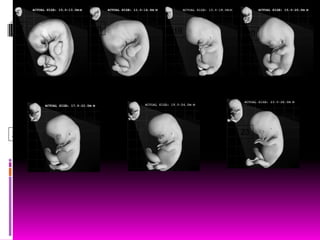

SEPTIMA SEMANA

 Séptima semana:

 Aparecen surcos entre los rayos digitales

 El intestino penetra en el celoma extraembionario,

herniación umbilical.

 Inicia la osificación de los huesos de miembros

superiores.

OCTAVA SEMANA

 Octava semana:

 Semana final del período embrionario

 Dedos de la mano notablemente definidos

 Surcos entre los rayos digitales de los dedos de los pies.

 Aún se encuentra la cola pero es gruesa y corta

 Al final los todos los dedos se alargan

 Ocurren movimientos de los miembros

 Se inicia la osificación de los miembros inferiores y se ve el fémur.

 Desaparece todo vestigio de la COLA.

 Al final el embrión tiene claras características humanas.

 La cabeza constituye casi la mitad del embrión.

 Son obvios los párpados

 El intestino se encuentra aún dentro de la porción proximal del

cordón umbilical

 Toma forma el pabellón auricular

• Note:

• Activity levels are

quite high at times.

Motion is very good

for developing

muscles and bones.

• Label Key:

• 1. foot

• 2. lower leg

• 3. left thigh

• 4. left knee

• 5. umbilical cord

• 6. head

• 7. left upper arm

• 8. abdomen

• 9. back

•

• All ages referenced

from date of

fertilization (or

conception), not last

menstrual